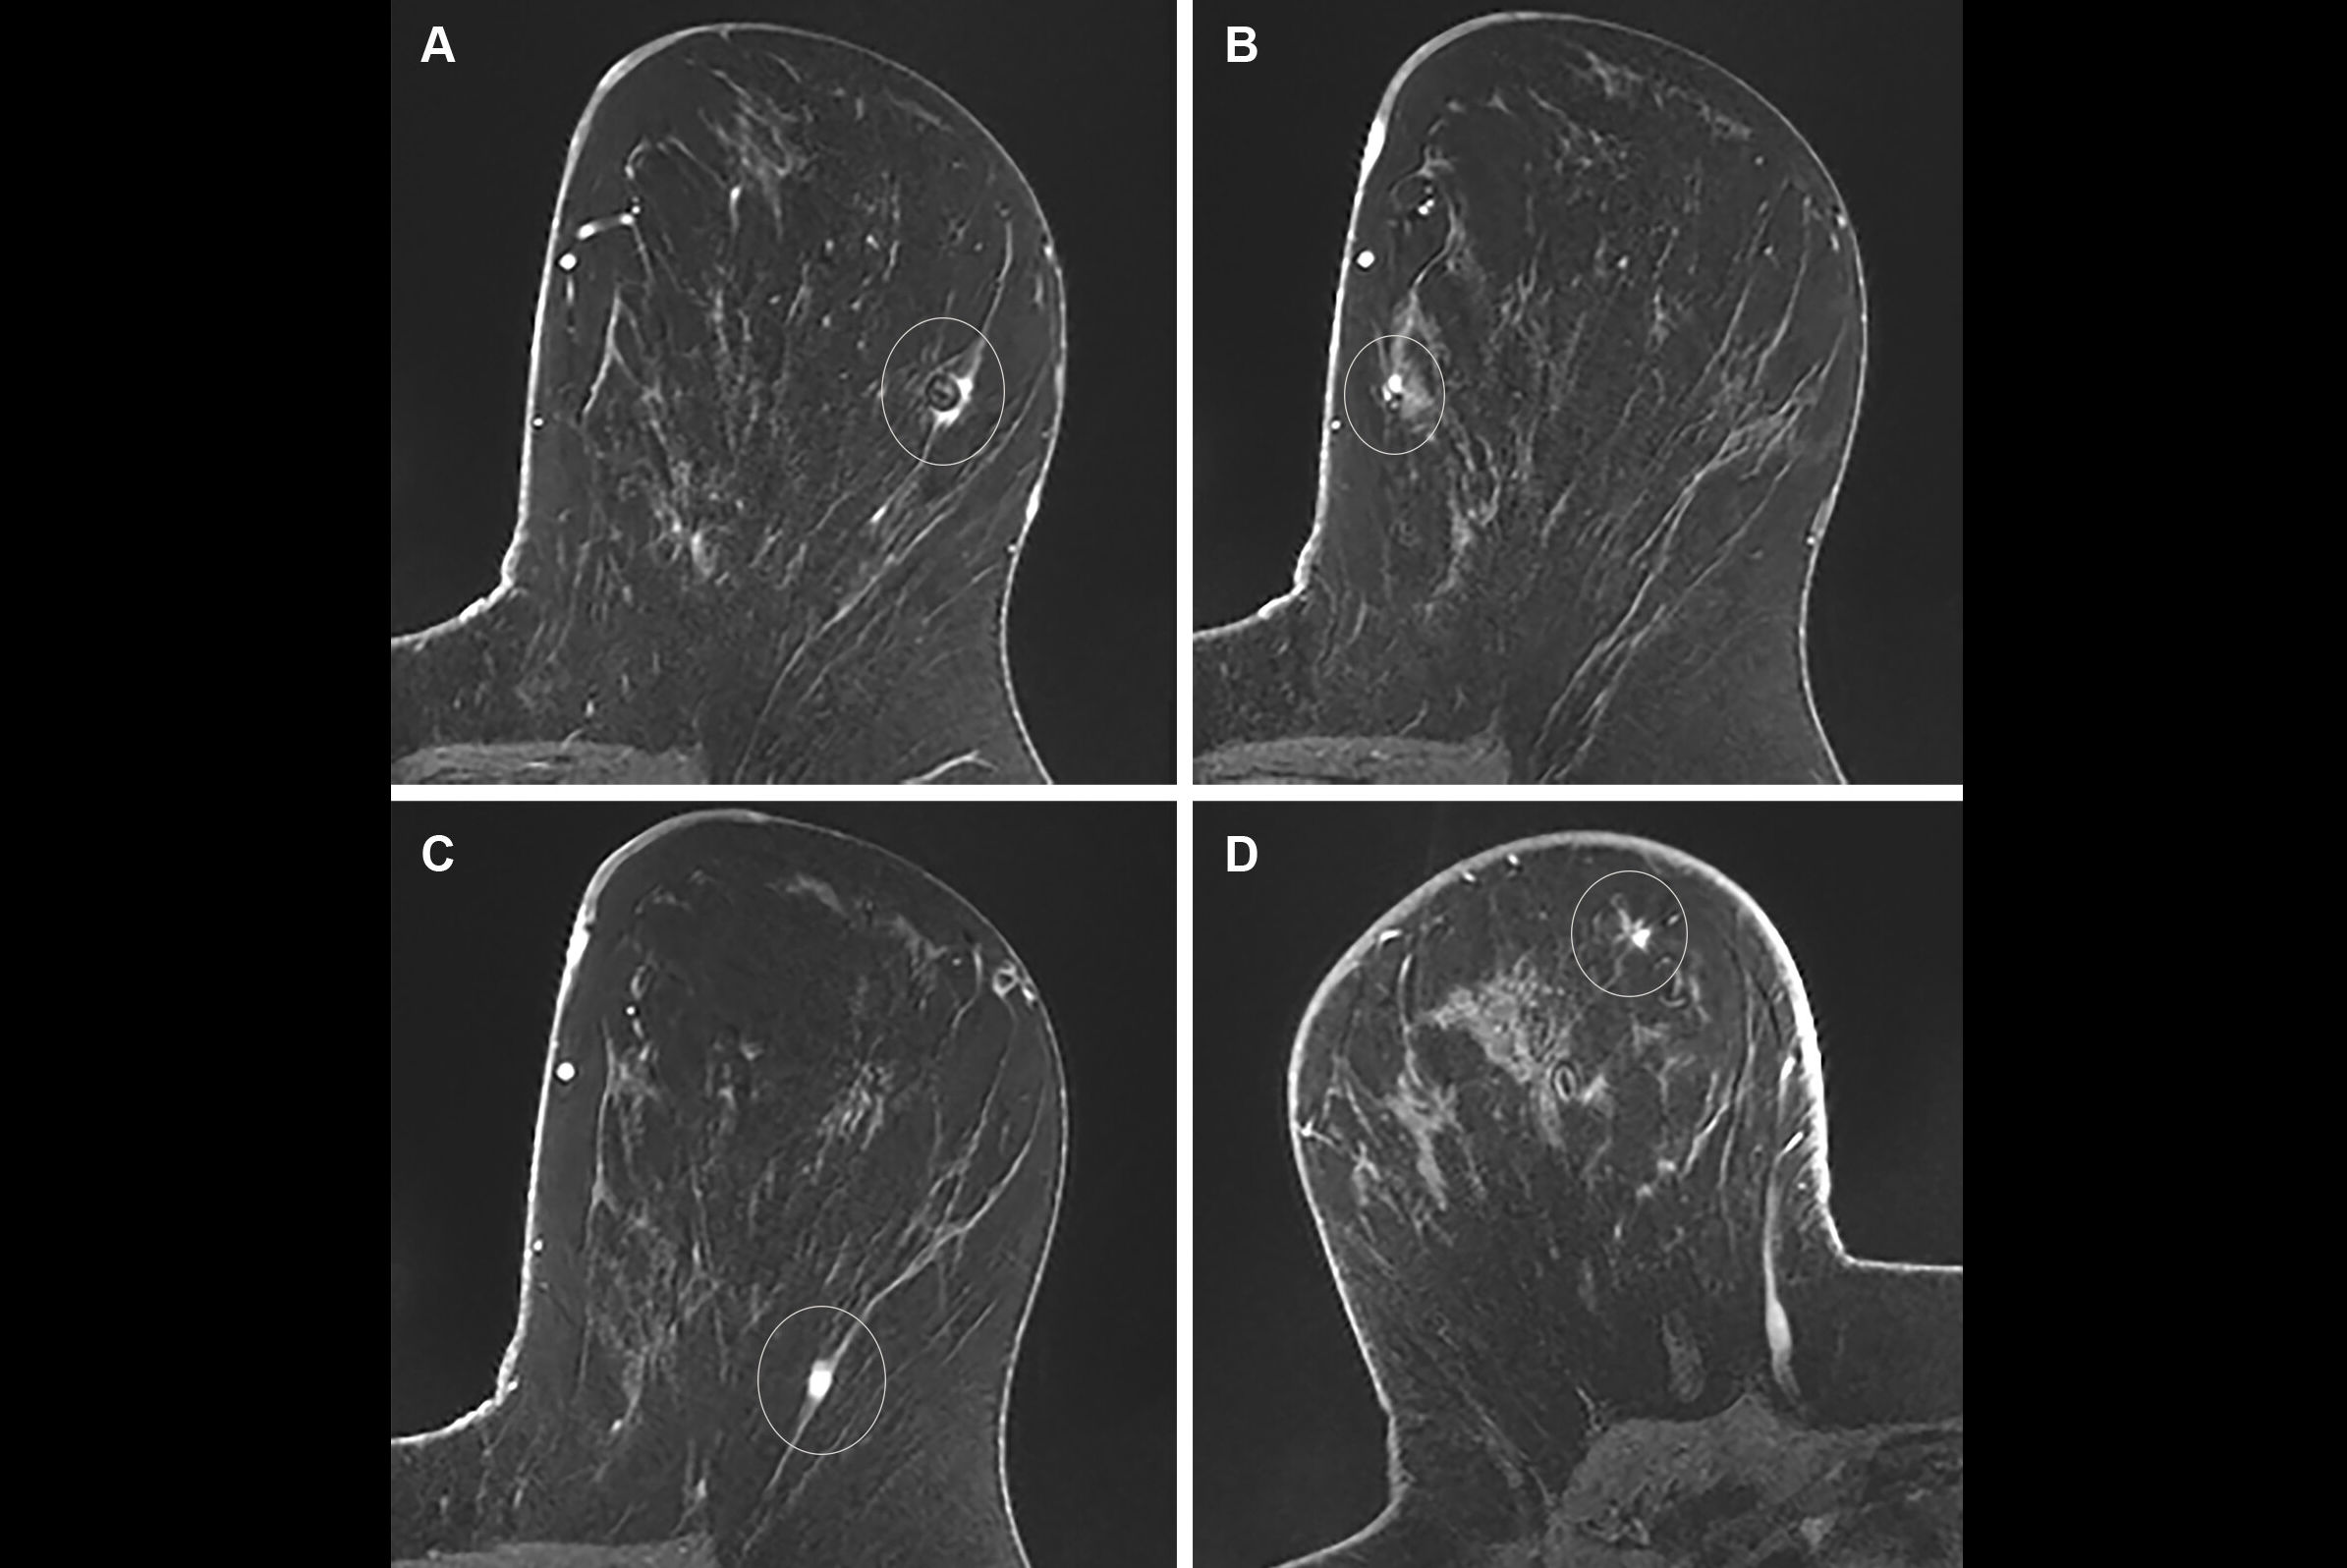

Node Reporting and Data System (Node-RADS) true positive: images in a 39-year-old woman who presented with a palpable mass in the right breast. (A) Axial contrast-enhanced fat-suppressed T1-weighted MRI scan reveals a 27-mm irregular, heterogeneously enhancing mass in the right breast (arrows). (B) Axial contrast-enhanced fat-saturated T1-weighted image from dedicated axillary MRI reveals a prominent lymph node (arrows) in the right level I axilla, measuring 9 mm in the short axis, with focal necrosis, an irregular border, and a displaced fatty hilum. Per the Node-RADS criteria, node size was normal, but the configuration criterion yielded a sum score of 4, resulting in a Node-RADS score of 4 (i.e., high suspicion for nodal invasion). Following breast-conserving surgery, pathologic examination confirmed grade III invasive ductal carcinoma, which was estrogen receptor negative, progesterone receptor negative, and human epidermal growth factor receptor 2 positive. A sentinel lymph node biopsy, followed by axillary lymph node dissection, revealed metastasis in two of the 11 dissected lymph nodes, both of which were macrometastatic.RSNA